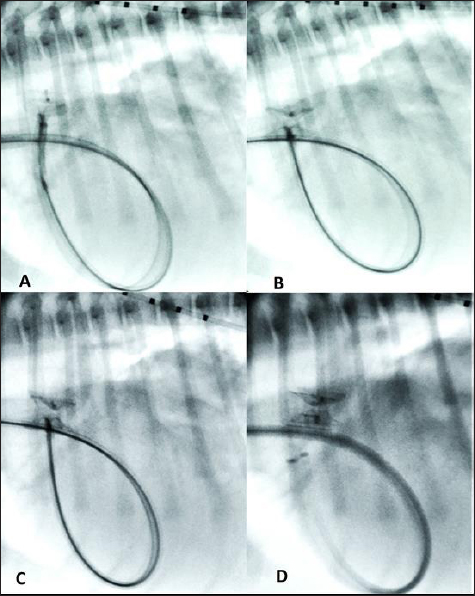

The device, previously screwed clockwise onto the delivery cable and introduced into its loader (SJM Amplaterz™ TorqVue™ Delivery 45° component 7 Fr. Loader and Delivery cable, AGA Medical Corporation, Plymouth, MN) was inserted into the delivery sheath and advanced carefully until the distal disc was expanded in the descending aorta near the PDA. The partially deployed mVSDO, attached delivery cable, and delivery sheath were then gently pulled back simultaneously until the distal disc engaged the ostium of the PDA and lodged in the ductal ampulla. The guiding sheath then was retracted further allowing expansion of the central component of the device within the PDA ampulla. The entire system was then retracted and subsequently, the proximal disk was expanded within the main pulmonary artery. The stability of the device was then tested with the push-pull “Minnesota wiggle” maneuver, the cessation of transductive flow and the correct positioning of the mVSD pulmonary disc were verified with transthoracic echocardiography, and the device was then deployed (Fig. 4). During the placement of the device all the parameters (saturation, invasive blood pressure, end-tidal CO2) remained within physiological ranges. Blood pressure increased (from 96/40/58 to 120/50/73 mmHg) while heart rate decreased (from 100 to 65 bpm) after occlusion of the PDA.

Fig. 4. Fluoroscopic sequence. (A) The first disc of the mVSD has been deployesd engaging the aortic side of the PDA and (B) then the waist and second disc fully extruded with the waist occluding the ostium and the second disc located into the pulmonary artery. (C) The stability of the device is tested with the push-pull “Minnesota wiggle” maneuver. (D) The device has been released